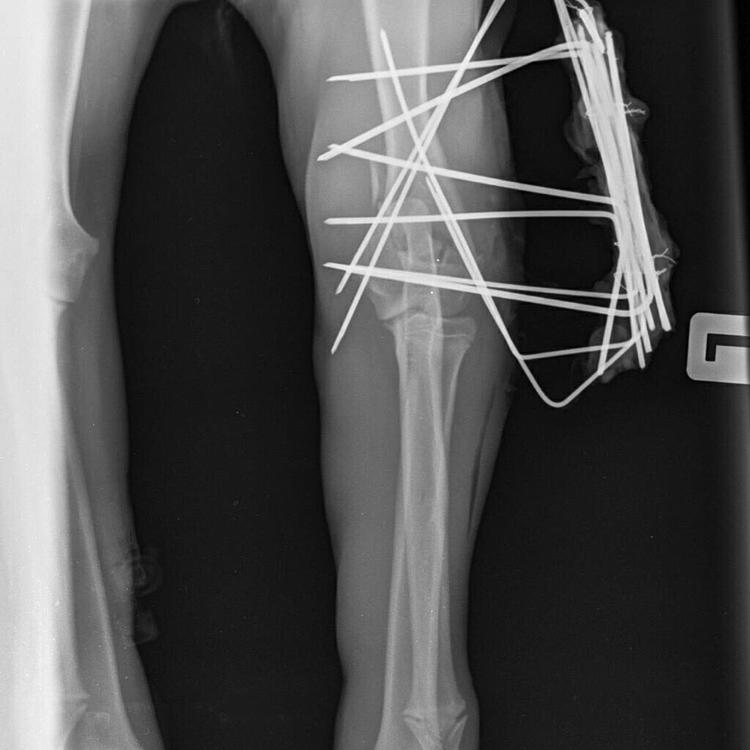

Stenveyz Опубликовано 19 мая, 2019 Опубликовано 19 мая, 2019 Где 6? 5 на передних я вижу, и 4 на задней. Вторая лапа не видна. Вот вчерашнее обновления в группе фонда.

Лея и мама Опубликовано 20 мая, 2019 Опубликовано 20 мая, 2019 Малыш абсолютно чудесный! Ласковый и трепетный. Прижимается к ноге и замирает от счастья что он не один. В машине стал весело погрызывать мне руку) очень не хочет быть один. Как только остался один в комнате поднял шум) но очень быстро успокоился. Лечить нужно и вторую лапку. После катетера осталась плохая рана. Сейчас ее обрабатывают и закладывают мазь. Ну ничего! Будем лечиться. Завтра утром поеду проведывать малыша. Спасибо всем неровнодушным, тем кто участвует в жизни малыша словом, делом и денежкой!